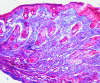

Fig. 7.

MT stain for group 1 (seventh-day sample).